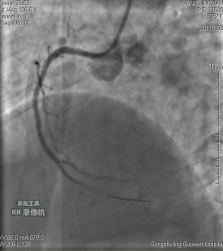

中日聯(lián)誼閆明洲教授向家屬交代病情及介入相關(guān)并發(fā)癥后,患者及家屬同意冠脈支架治療,過(guò)程順利,于右冠脈中段植入Firebird2 2.5*33mm 藥物洗脫支架1枚。

術(shù)前 術(shù)后

患者冠脈支架植入術(shù)后,胸骨后疼痛癥狀明顯好轉(zhuǎn),復(fù)查心電圖抬高的ST段回降。